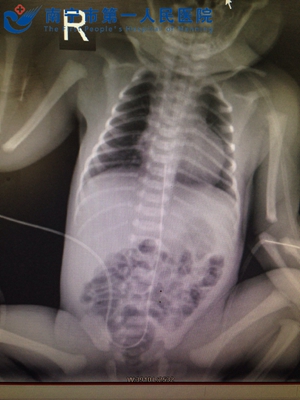

——南宁市第一人民医院新生儿科成功开展脐静脉置管技术脐带,是母亲与宝宝的生命桥梁,是保证宝宝的健康发育的生命通道,但早产儿因胎龄过小,各系统发育不成熟,抵抗力低下,一旦离开母体难以继续生存,这时候就需要在脐静脉内置管,给予宝宝继续存活的各种营养物质,开通人工的生命通道。我院新生儿科开展新生儿脐静脉置管术已近1年,是广西区内开展该技术的第二家医院,共行脐静脉置管术83例,手术均取得成功,挽救了许多早产儿、危重患儿的生命...